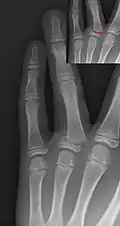

Salter–Harris III fracture of big toe proximal phalanx. -